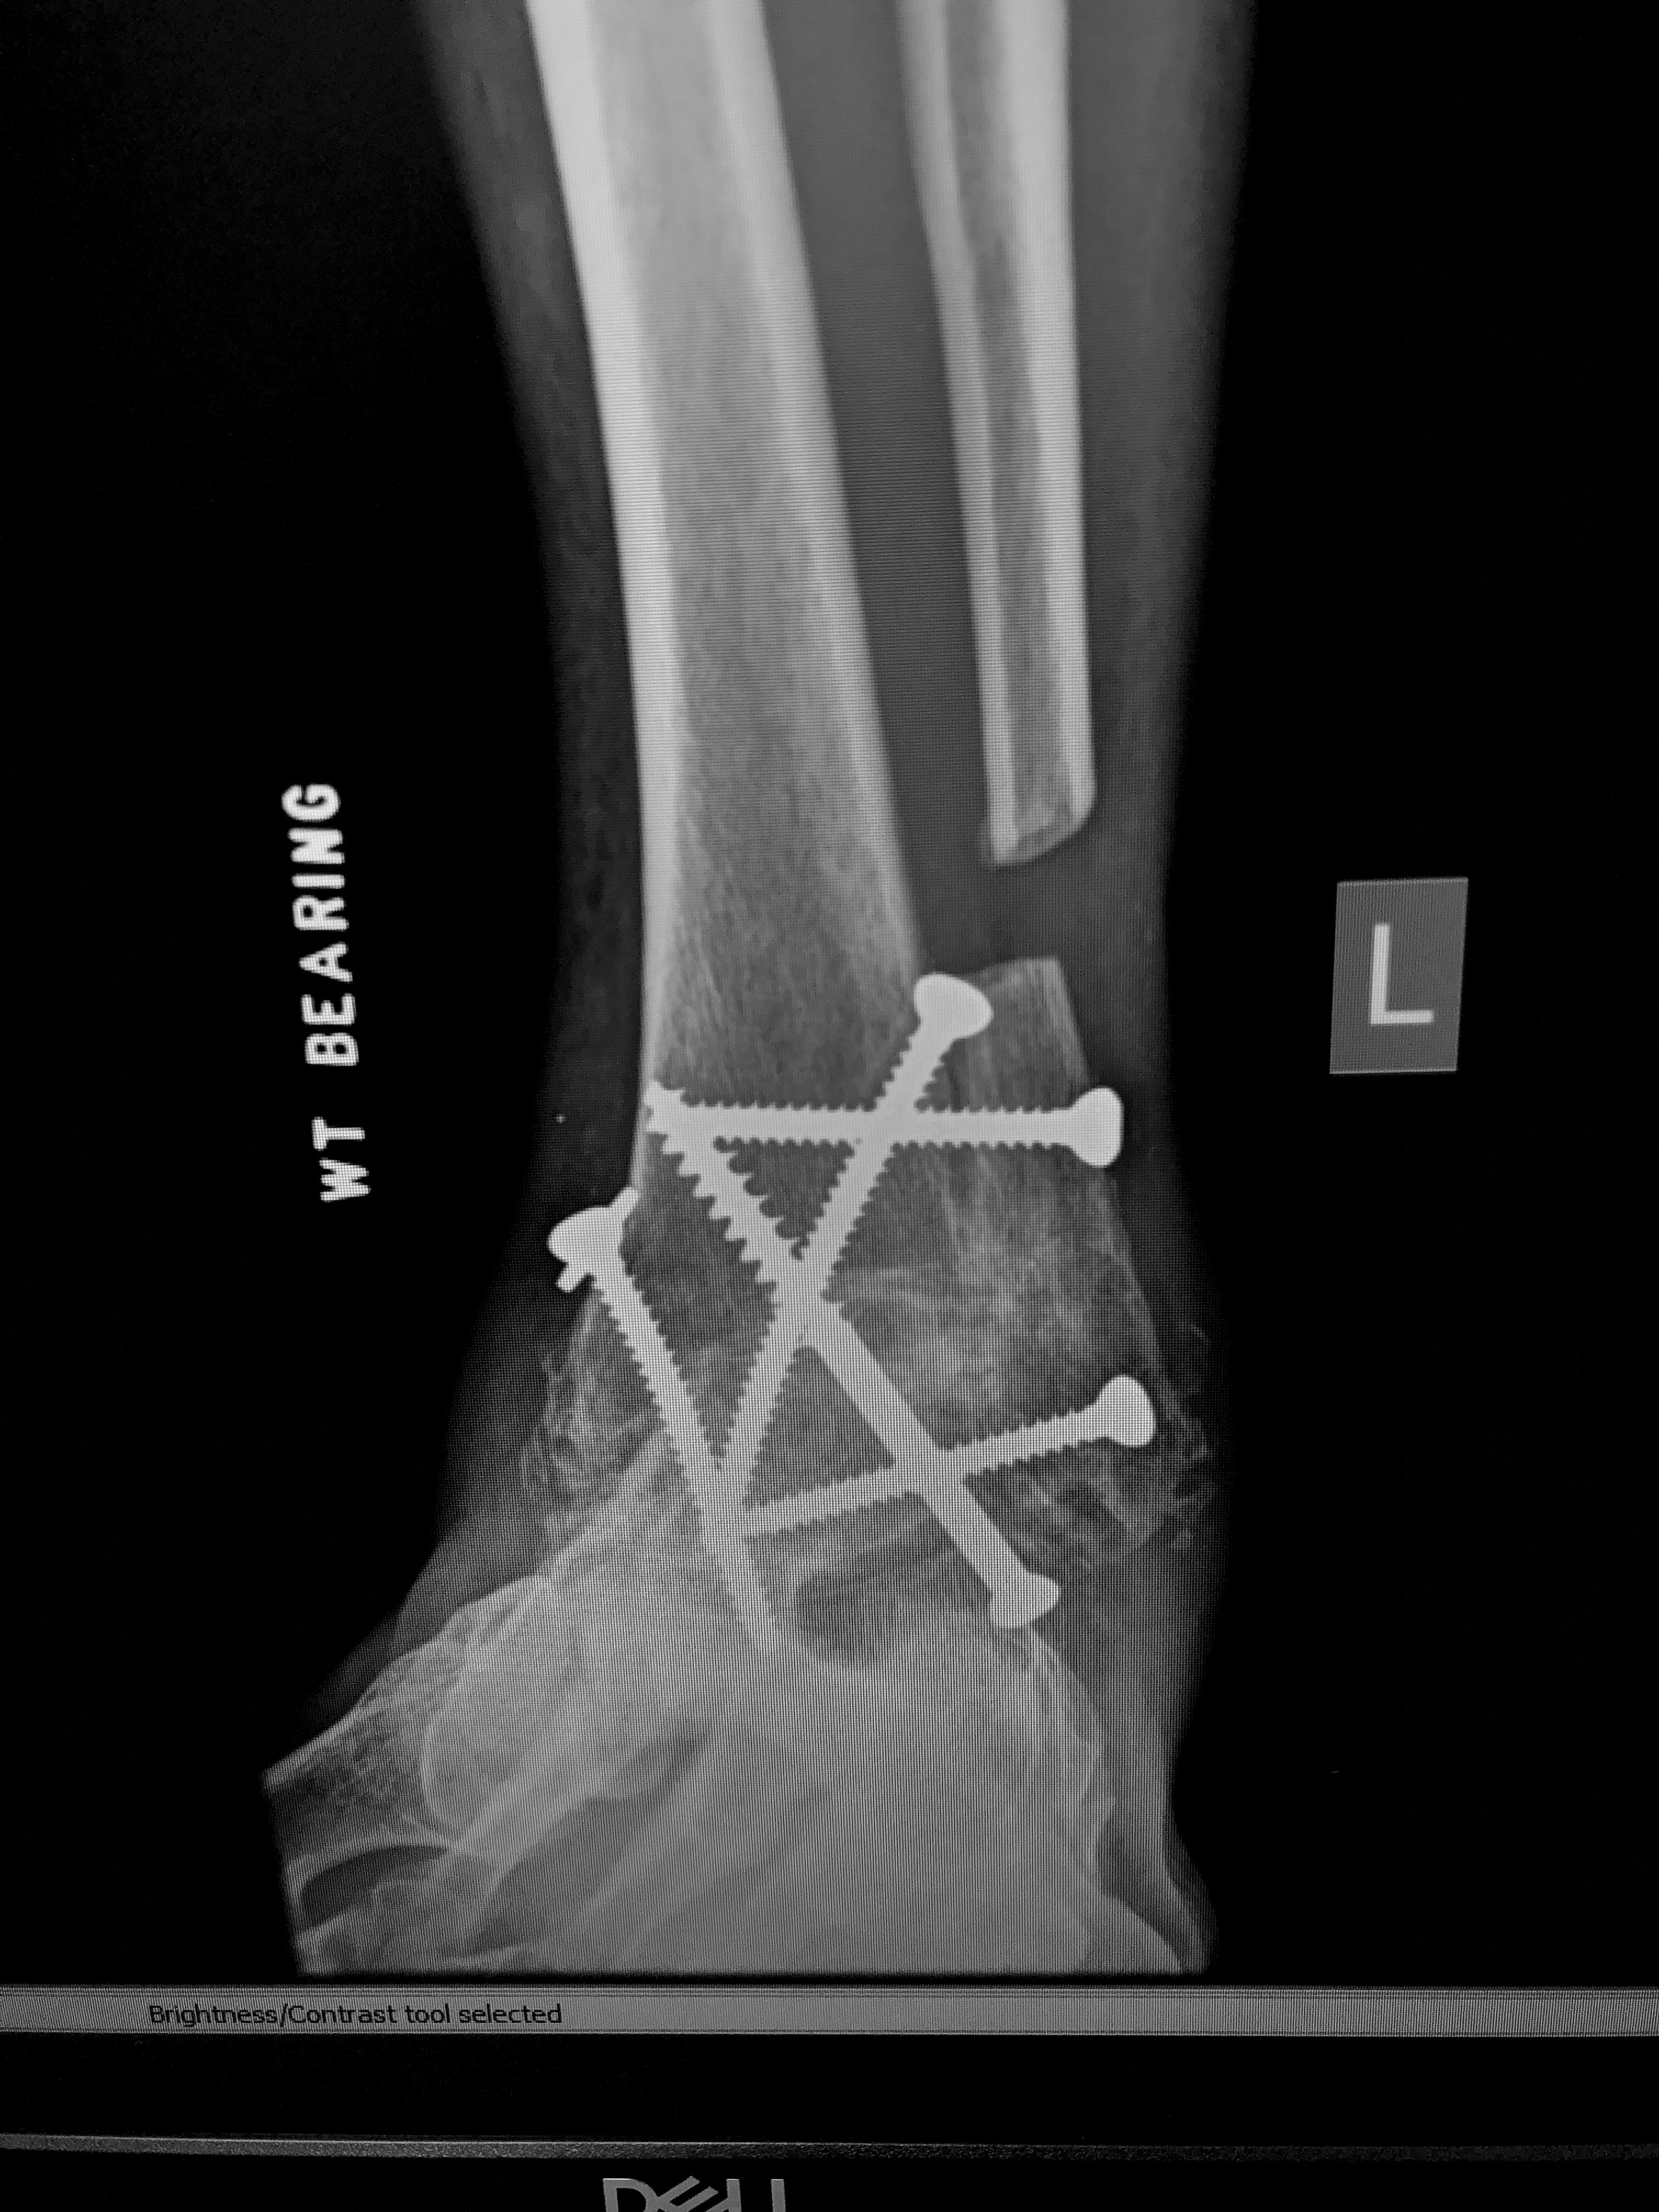

He started to hike up hills faster again. Two hip replacements and a fused ankle (5 screws through his ankle bones, a fixed 90 degree angle, and a floating fibula). Push. Red face. Sweat. Elevated heart rate. Sucking oxygen. He didn’t have the balance and ease he once had but he kept taking steps. Mark started tracking workouts again. Timing. First, just with Easton and then on his own. Did Easton save him? His by his side companion. He’ll walk with you too, Mark. Sometimes, it’s easier to care for another than to care for ourselves. Sometimes, the most treasured relationships of our lives accomplish both. Ayoooooooo!